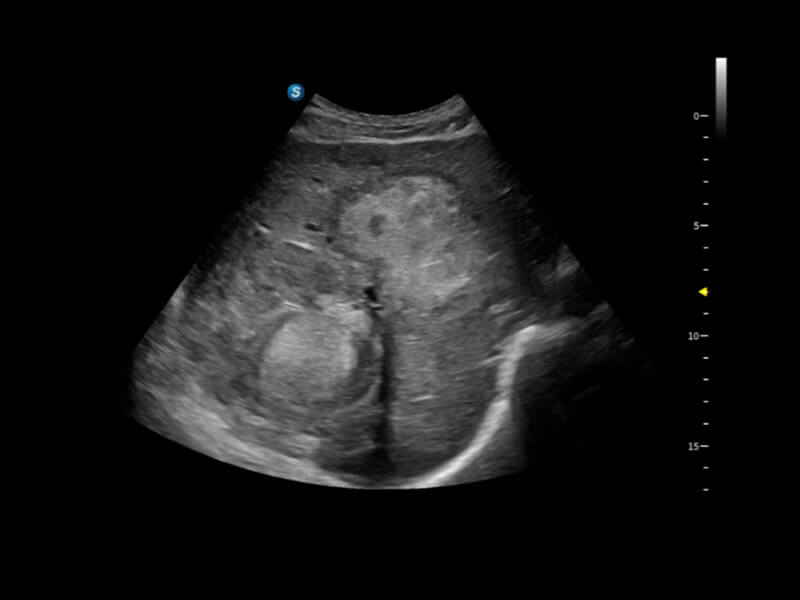

作为开立医疗全新打造的超高端旗舰超声产品,从探头抬起唤醒开启扫查到多维探头发射接收,通过先进的场成像发射、自适应聚合重建等技术,基于RF Data原始射频数据在图像生成、高端功能等方面实现突破,提供多科室综合临床解决方案。

S80 提供多样化超声成像技术,可满足不同科室的需求,在助力扫查诊断和介入治疗中发挥着重要作用。